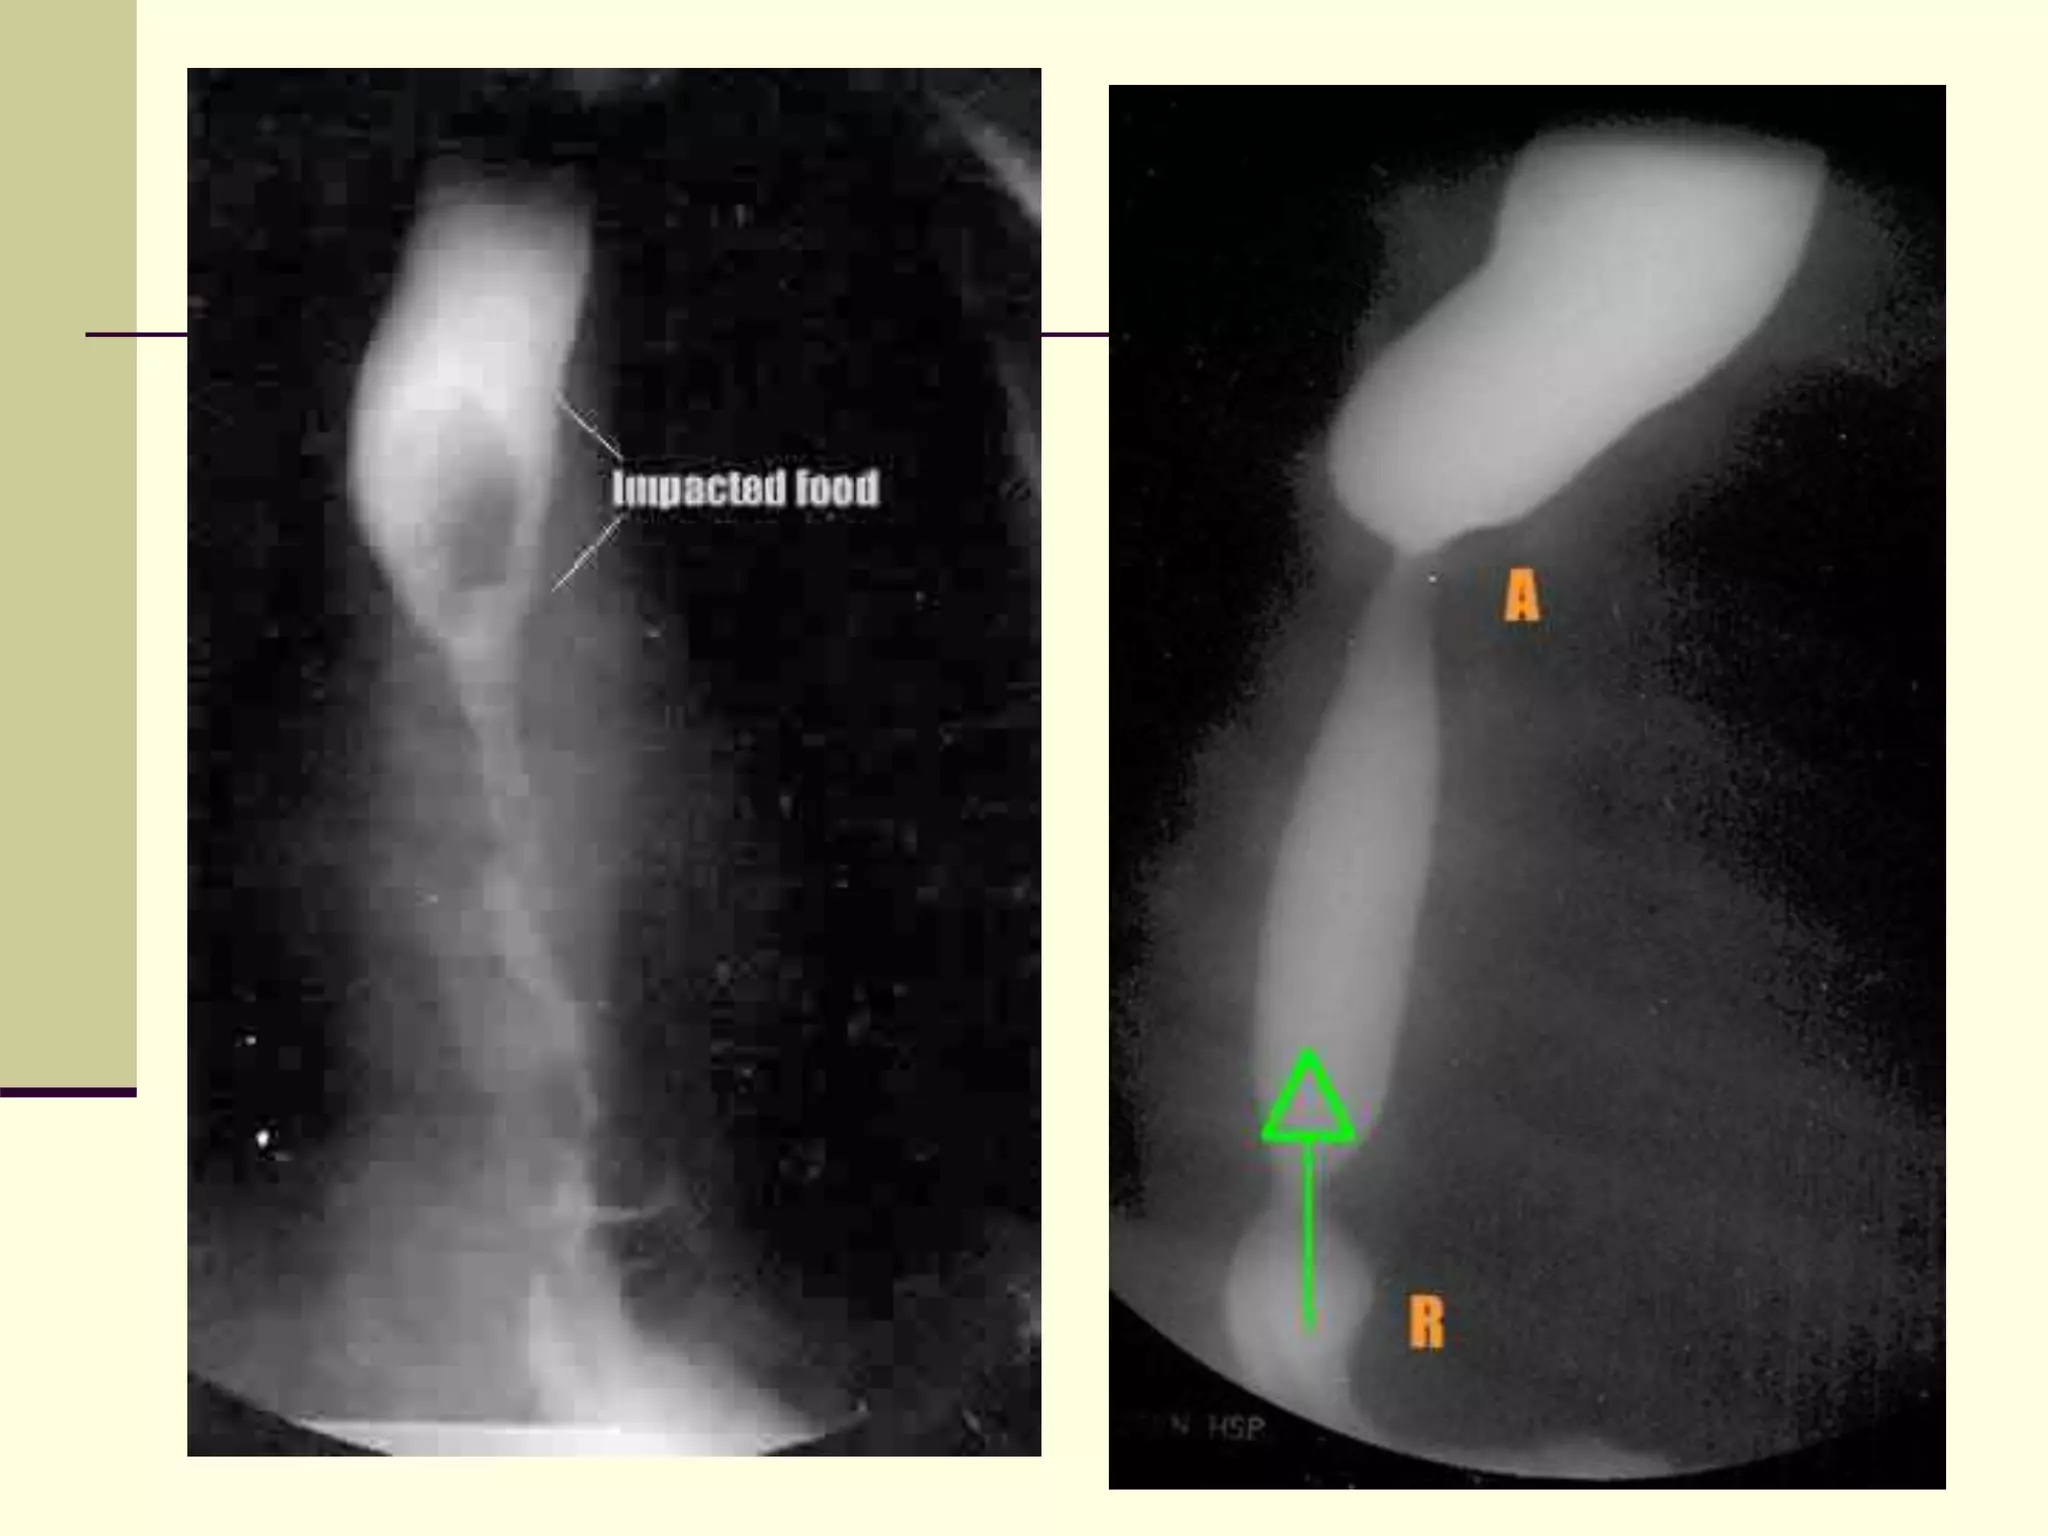

 This is a contrast study

demonstrating long-gap

esophageal atresia. A dilator

is placed within the

esophageal pouch and

contrast is instilled into the

stomach.

 A distance of 5.5 vertebral

bodies is seen between the

esophageal remnant and the

stomach